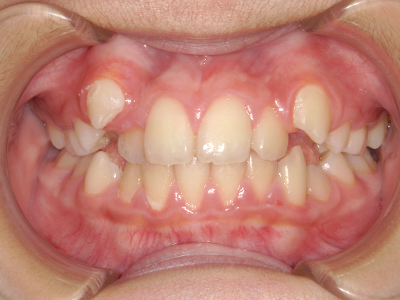

歯並びの相談に来られるお子様は、口呼吸をしているケースが多く、これが歯並びに大きな影響を与えています。

↓ - さまざまな不正咬合が生じる